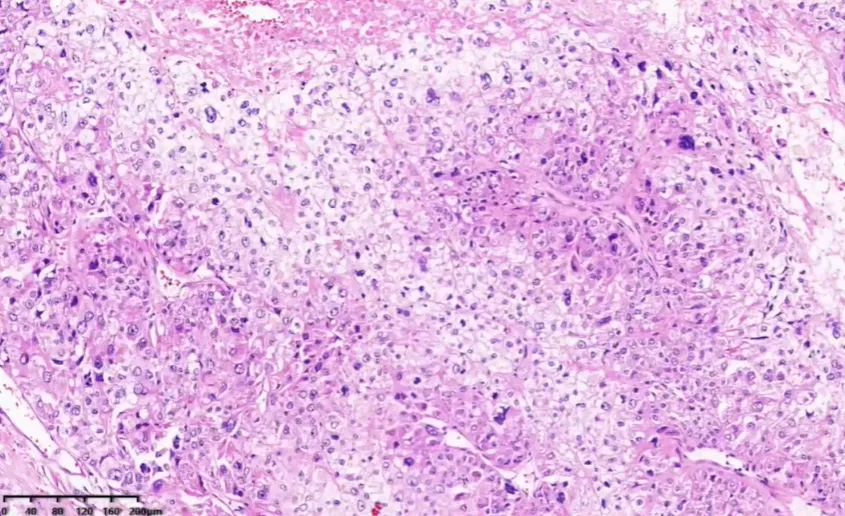

病例2

手术所见(2024.8.8):右侧髂窝处巨大肿物约 10×9cm,灰白质硬,布满怒张血管,沿腹主动脉右后壁多发肿大淋巴结,较大者直径 3cm,且融合成团。

胞浆嗜酸或透亮,细胞异型性大,可见瘤巨细胞。

肿瘤性坏死

脉管内瘤栓

网状纤维染色。网状纤维结构破坏。厚壁不均。

🌺 病理诊断:肾上腺皮质癌。